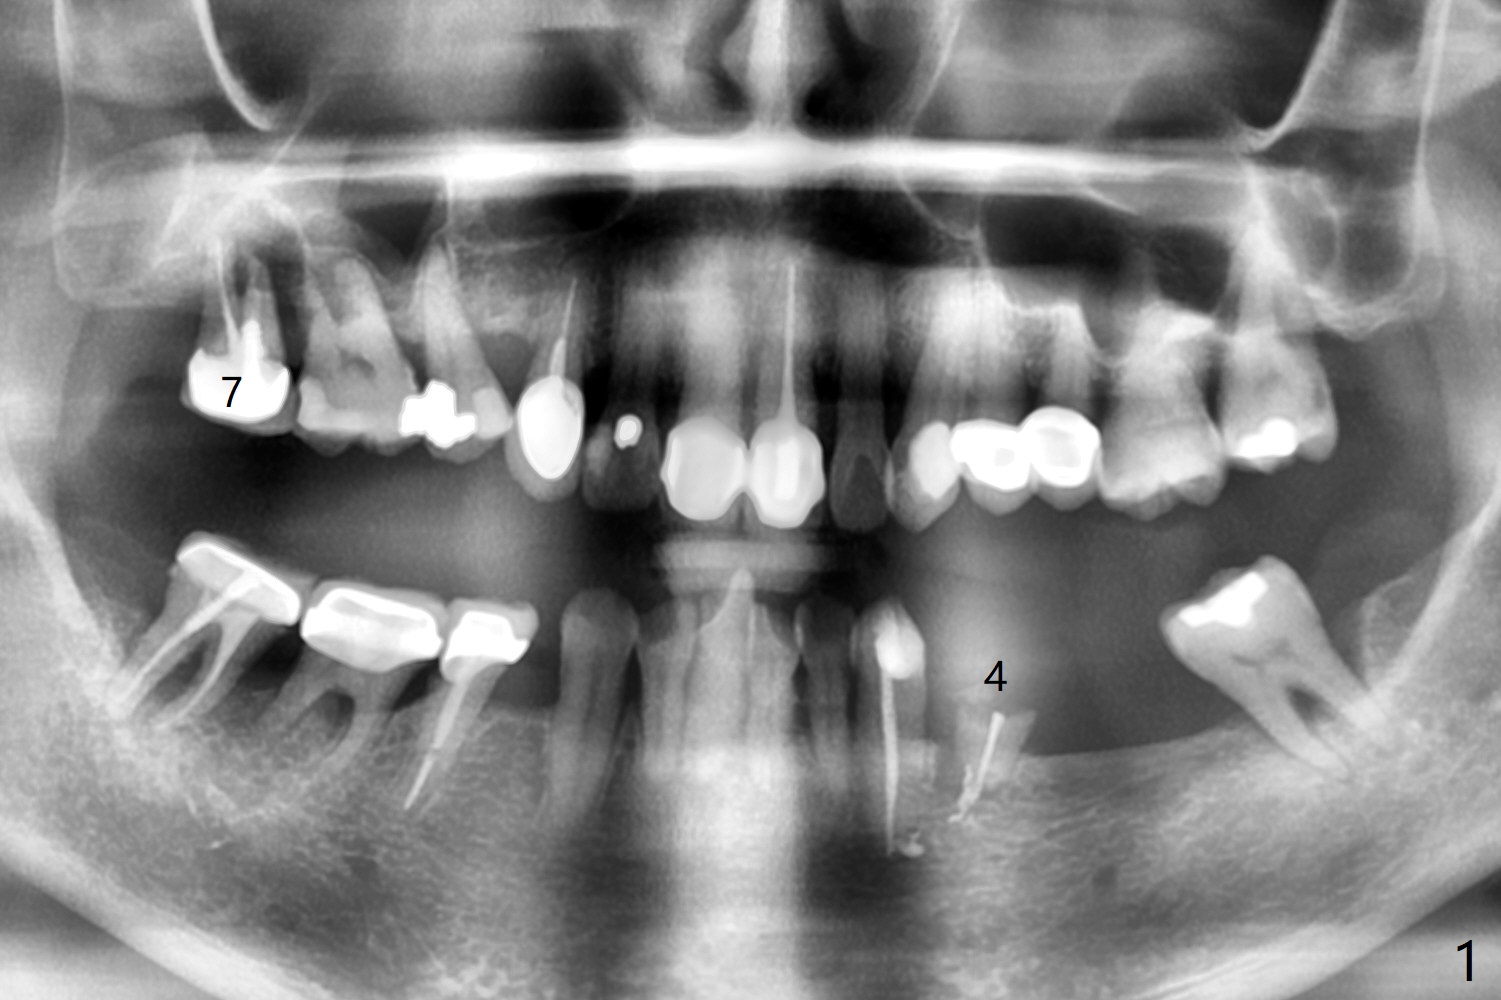

59岁女右上七骨质吸收严重(图一),上颌窦底板薄(图二:*),而窦膜厚(图三:*),应该容易提升,腭侧根吸收(图四:P),上颌窦底板穿孔(图五:*),拔牙后(图六:黑色),水提升(白箭头),放置PRF膜(黄色曲线)和粘性骨块(红色圆圈),最后完成位点保留(图七:大圆圈),放置另外一块PRF膜和6个月吸收膜,缝合,牙周或者树脂敷料。Return to No Deviation 19-21 位点保留后 导板与张口度 Xin Wei, DDS, PhD, MS 1st edition 09/09/2020, last revision 01/01/2021